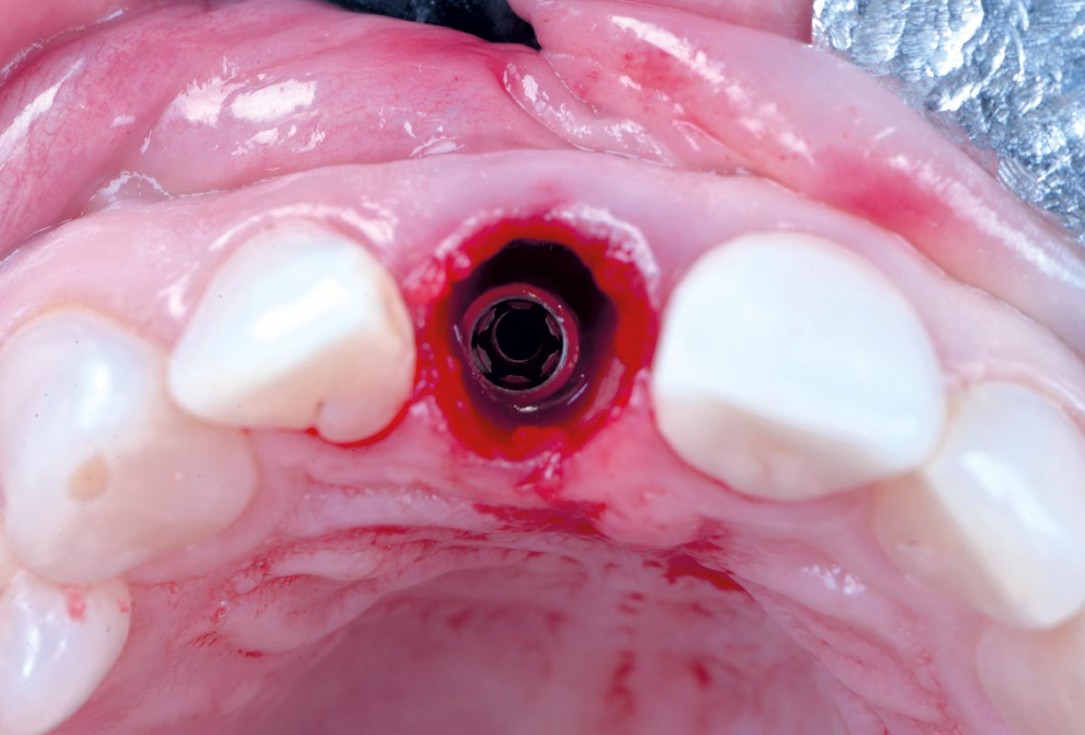

10/30 - Occlusal view – 4 mm placement depthExcellent aesthetic result of buccal augmentation with mucoderm® and maxgraft® after immediate implant placement - 3-years follow-up - Dr. A. Puišys